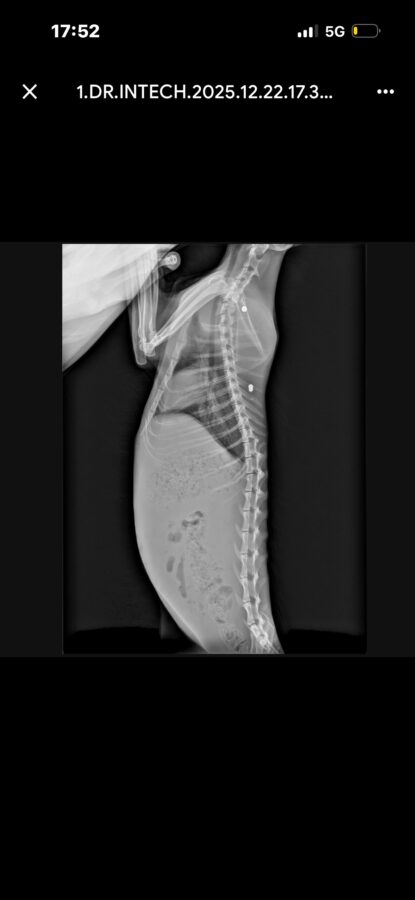

Las radiografías realizadas al animal confirmaron la presencia de dos proyectiles compatibles con perdigones, lo que apunta a un acto intencionado de violencia contra los animales

Las radiografías realizadas al animal confirmaron la presencia de dos proyectiles compatibles con perdigones, lo que apunta a un acto intencionado de violencia contra los animales. El caso ha sido hecho público por personas voluntarias dedicadas a la protección y cuidado de colonias felinas en Fraga, que alertan de la gravedad de lo ocurrido y de la vulnerabilidad de estos animales.